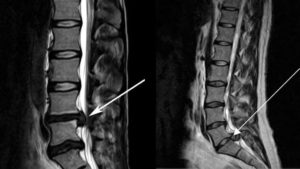

Киста пояснично-крестцового отдела на МРТ